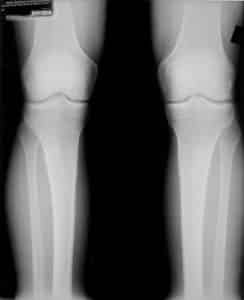

Kijkt u eens naar de volgende röntgenfoto’s. In de eerste foto ziet u dat er kraakbeenverlies is in de rechter knie. Deze cliënt werd geadviseerd om de rechterknie te laten vervangen (klik voor een vergroting).

Wat ook te zien is, is dat het rechter bovenbeen scheef staat ten opzichte van het onderbeen. Door deze scheefstand slijt de rechterknie ongelijkmatig aan de rechterkant en krijgt kraakbeen niet de kans om te herstellen.

Onderstaande röntgenfoto is genomen na het doorlopen van een behandeltraject in de Egoscue kliniek van Austin, Texas. De foto is 15 maanden later genomen.

Zoals u hopelijk kunt zien, heeft het kraakbeen in de rechter knie zich hersteld na een behandeltraject met houdingscorrectie. Door de spieren en gewrichten te trainen is ook de hoek tussen onder- en bovenbeen weer normaal geworden en als gevolg hiervan heeft het kraakbeen de kans gehad om terug te groeien (en niet weer afgesleten te worden).